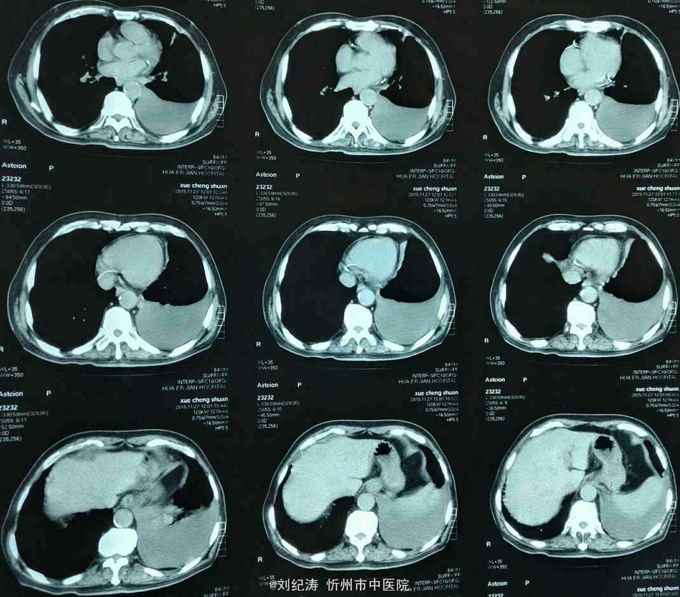

查体:ECOG评分:3分,生命指征平稳,浅表淋巴结未触及明显肿大,双眼睑无水肿,唇无发绀,颈软,双侧胸廓对称,左肺语颤增强,左肺呼吸音消失,右肺呼吸音粗,可闻及哮鸣音,心律齐,腹平软,肝脾肋下未触及,移动性浊音阴性,肠鸣音3次/分,双下肢无水肿。 辅助检查:血常规(2016.1.1):WBC:10.6*109/L,RBC:4.69*1012/L, PLT:165*109/L ,HGB:167g/L.生化(2016.1.1):谷丙转氨酶11U/L,谷草转氨酶11U/L,总蛋白60g/L,白蛋白33g/L,尿素:9.8mmol/L,肌酐:123umol/L,尿酸:251 umol/L,血糖:7.37 mmol/L;电解质:钾:4.79mmol/L,钠:123.5 mmol/L,氯:85.7 mmol/L,钙:2.03 mmol/L。肺部CT(2016.1.1):左肺完全萎缩,左侧胸腔大量积液,右肺未见异常,纵膈轻度右移,未见明显肿大淋巴结。